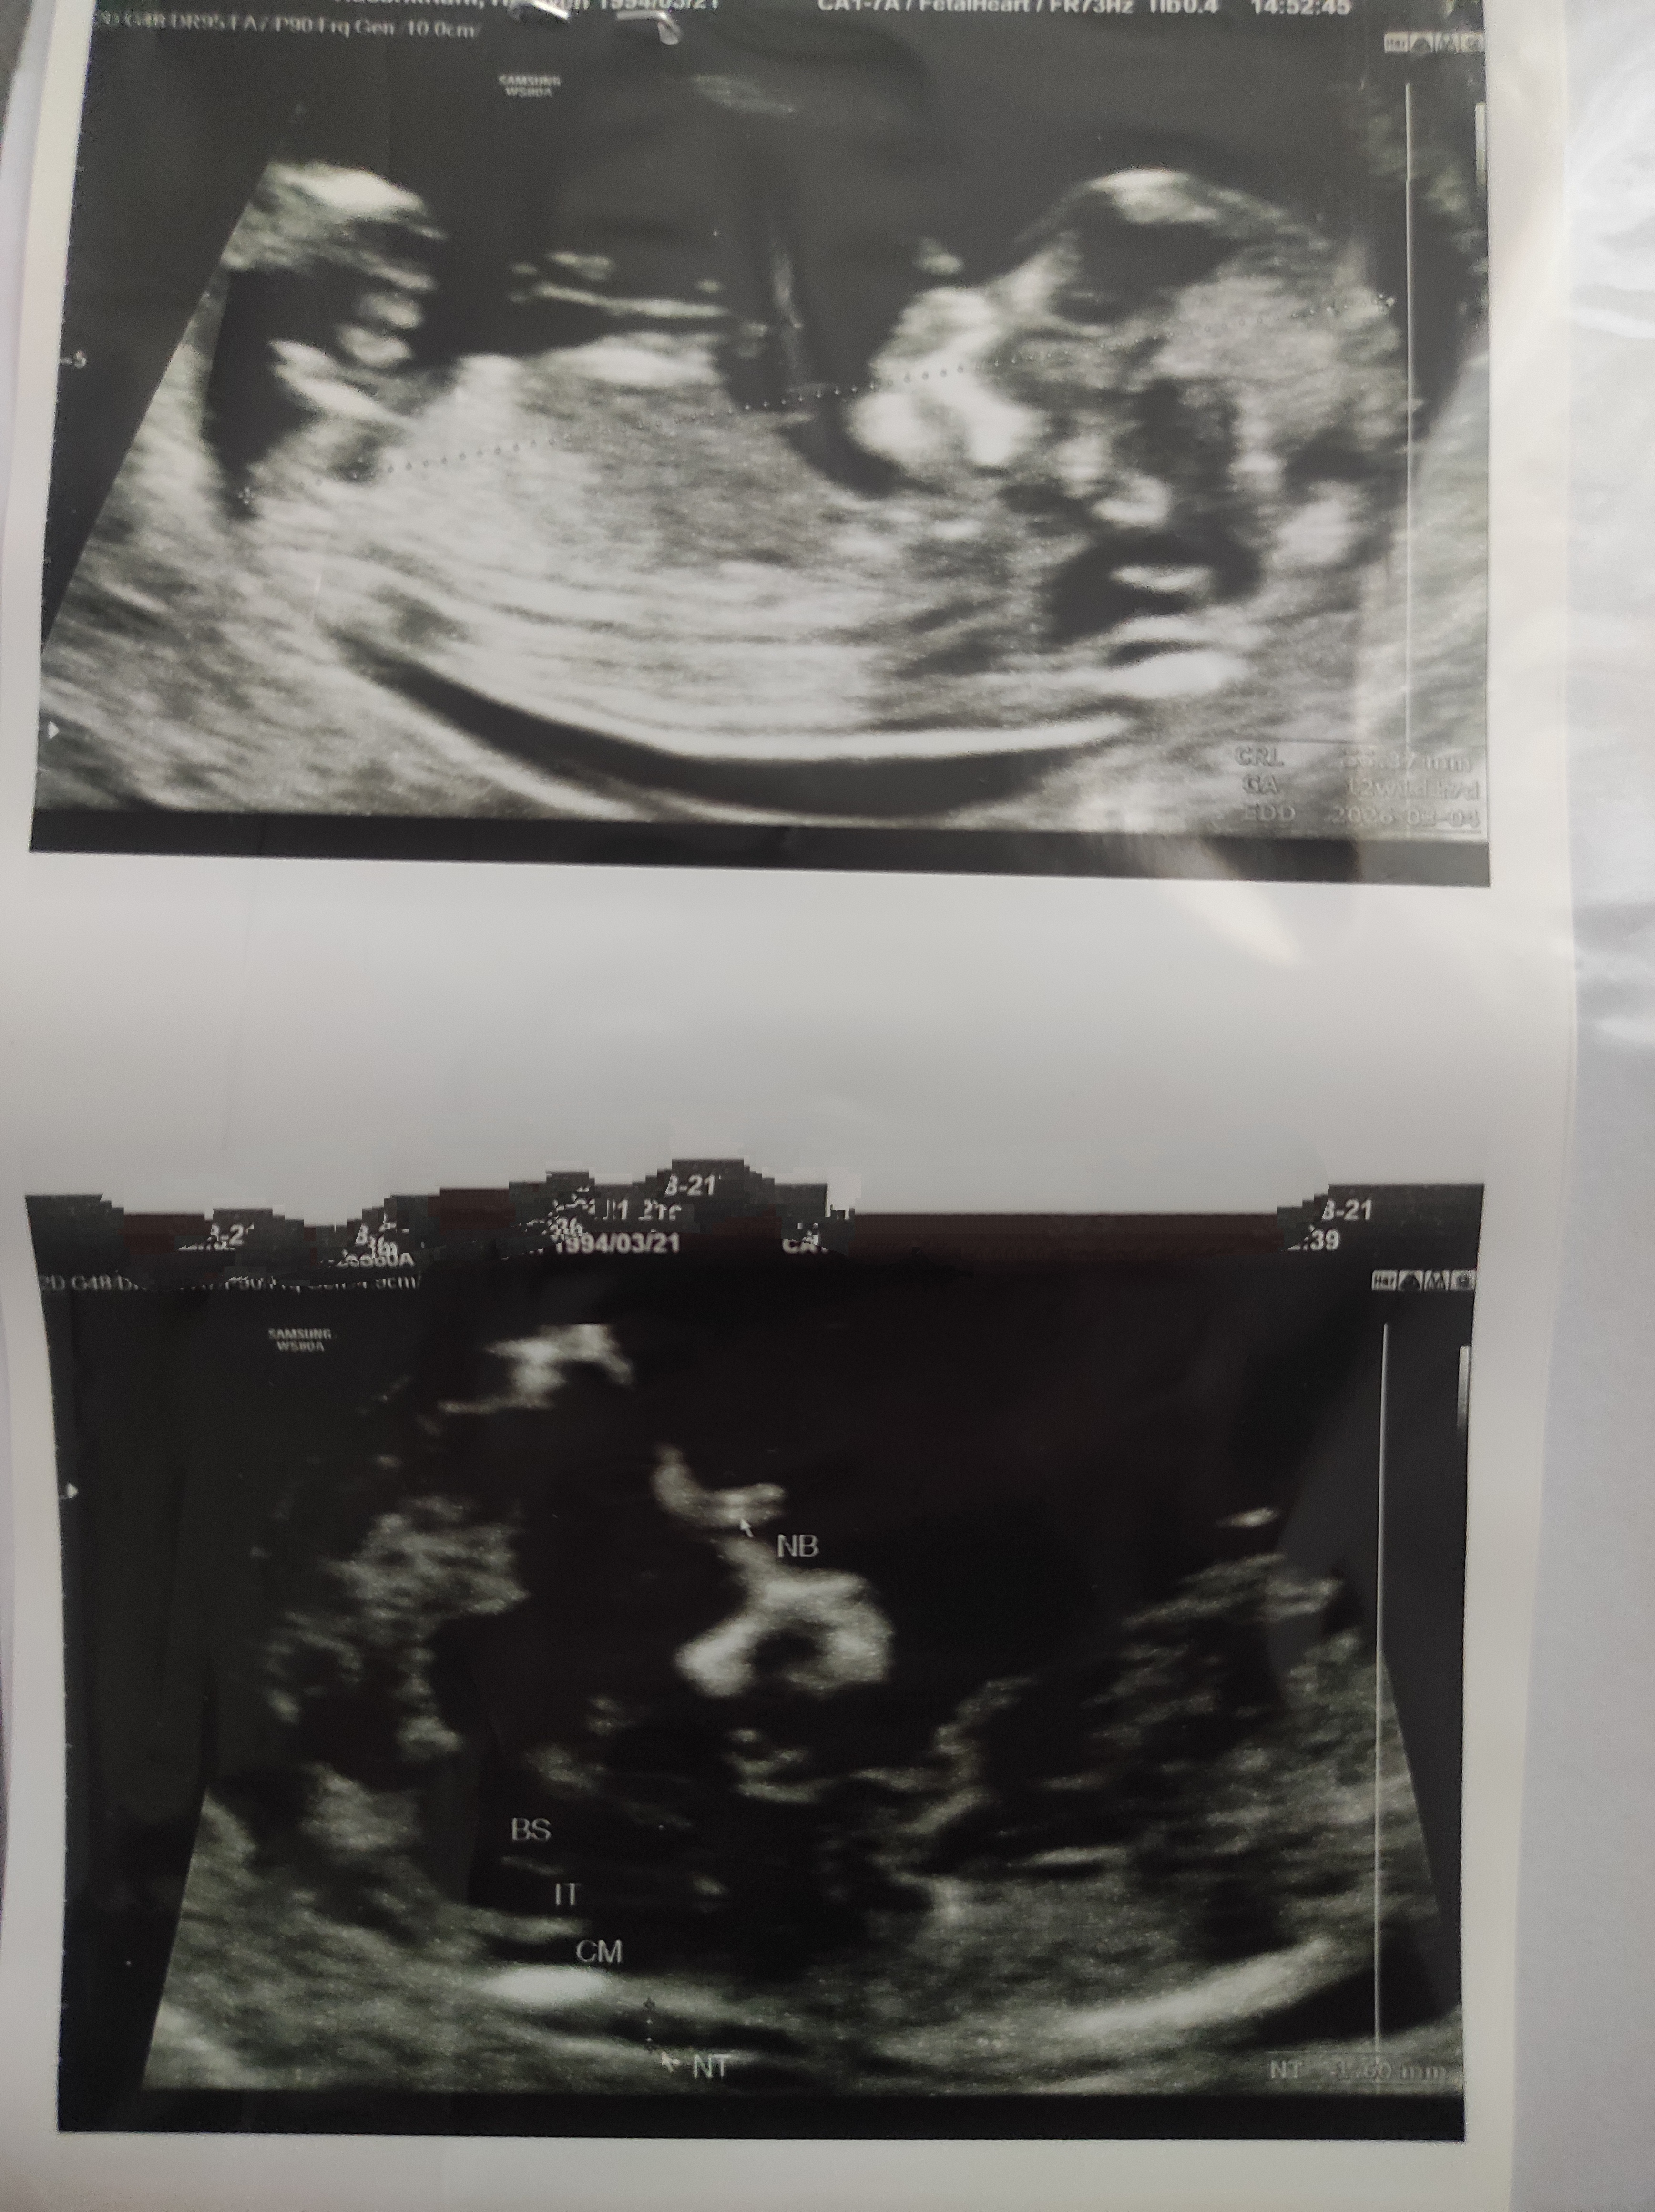

عکس سنو ان تی و جنسیت

اینم دختره جنست جورشد🥰هرچی بیشتردقت میکنم بیشتر مطمعن میشم دخملیه😍

احتمال هم نداد یعنیامامن چیزی که میبینم دختره چطور سونو نفهمید

احتمالا دختر

دختره😘